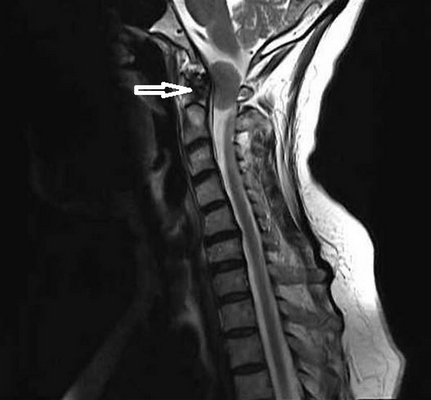

Опухоль краниовертебральной области (обозначена стрелкой)

Аномалия Арнольда-Киари

Это врожденный порок развития, при котором мозжечок и продолговатый мозг расположены атипично (в позвоночном канале).

До появления метода МРТ диагностика данной патологии вызывала большие затруднения, так как другие способы лучевой диагностики не дают четкой визуализации этих структур. В 80% случаев аномалия Арнольда-Киари сочетается с сирингомиелией (множественные кисты в спинном мозге), которая тоже диагностируется только на МРТ.